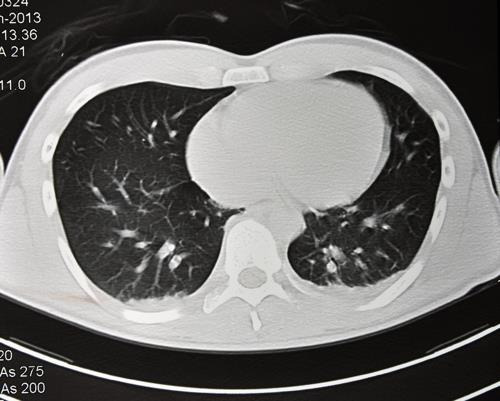

- 저선량 CT 검사: 조기 폐암 발견을 위해 권장되는 검사로, 방사선 노출을 최소화하면서 폐 내부의 미세한 변화를 감지할 수 있습니다. 특히 흡연자나 폐암 가족력이 있는 경우 정기적인 저선량 CT 검사가 권장됩니다.